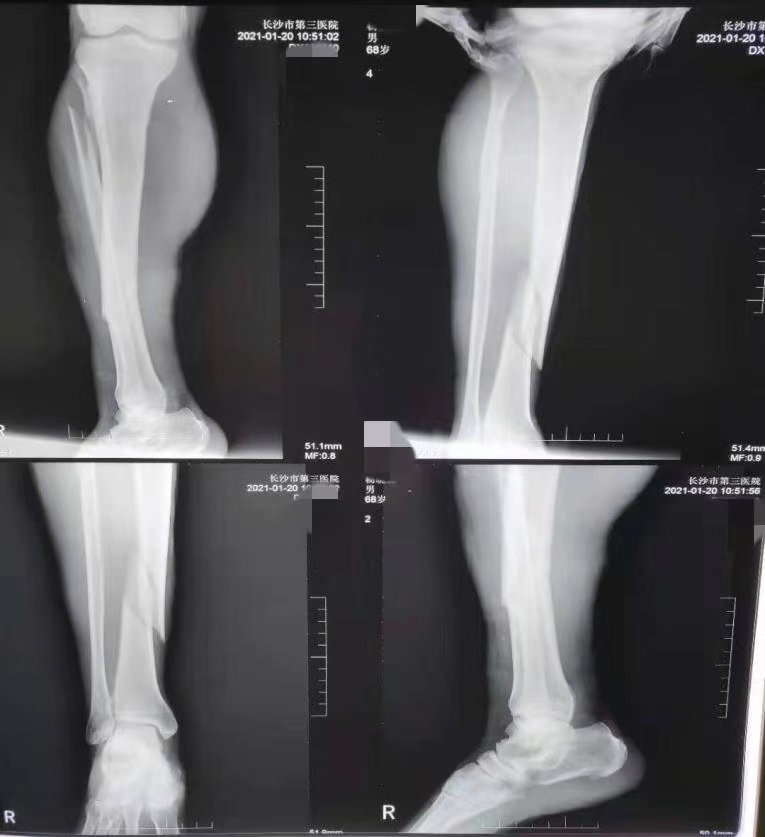

该院骨科二十一病室副主任医师王康为杨大爷检查时发现,老人右大腿大片淤青, X线照片显示右胫骨中下段螺旋形骨折,右腓骨中上段斜行骨折。骨科团队立即开通绿色通道,紧急为杨大爷行右胫骨骨折闭合复位髓内钉内固定术。手术非常顺利,术后杨大爷右大腿疼痛明显减轻。